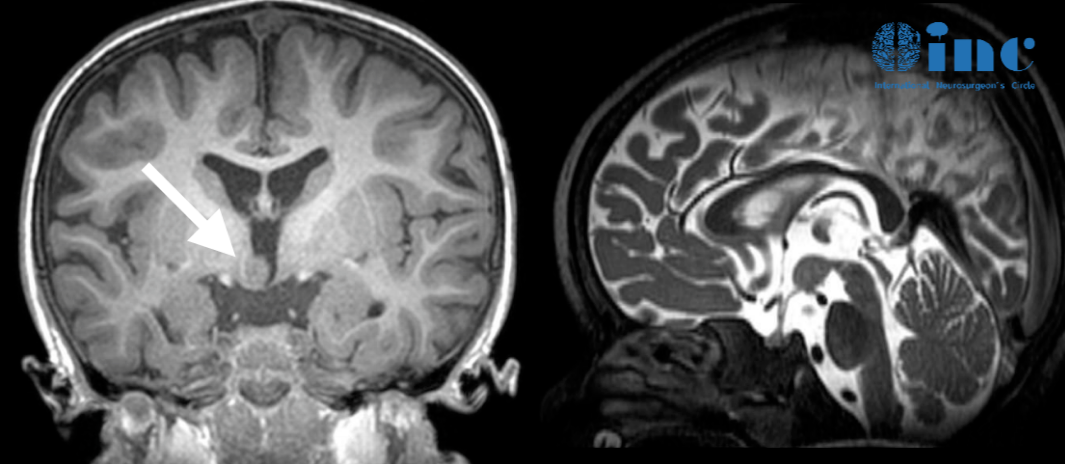

檢查結果告訴了他們真相:利利的顱內下丘腦錯構瘤導致了癡笑樣癲癇的發(fā)作。由于癲癇檢查復雜,醫(yī)生便交代他們,需要密切關注孩子癲癇發(fā)作的次數(shù)和頻率,即時記錄孩子的發(fā)作情況。

mri影像